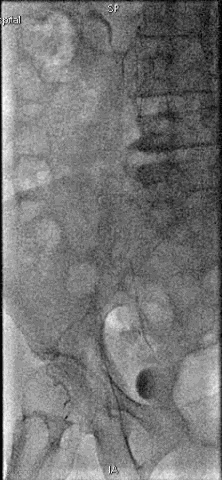

手术过程

抽吸结果